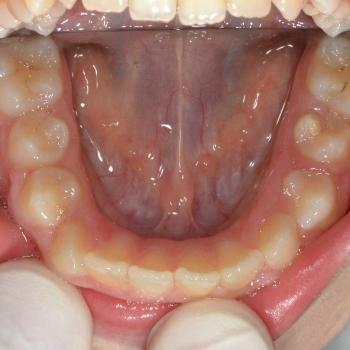

Virág és édesanyja esztétikai okokból, a kiálló és réses felső metszőfogak miatt kerestek fel. Az első konzultáció alkalmával ezen túlmenően felfedeztünk torlódást az alsó fogívben, mélyharapást és az alsó középvonal eltolódását.

A kezelési terv természetesen az összes problémát figyelembe vette, mégis a felső metszőfogak hátradöntésére koncentrált. A problémák megoldásához rögzített fogszabályozót, EVA-platte harapásemelőt, nyaki húzású headgeart és különböző intermaxilláris gumikat használtunk.